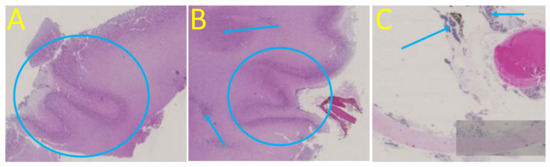

3. Case Report